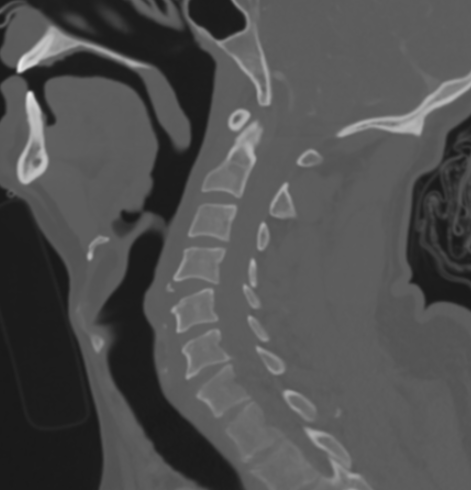

Xray / CT

Large antero-inferior body fragment / tear drop

- > 20 %

- stays attached to ALL

+/- posterior superior fragment retropulsed into canal

Anterior column fails under compression

- hearing of the anterior vertebral body

- rupture of the ALL

- disruption of the discoligamentous complex

Posterior column fails under tension

- disruption of PLL

Retrolisthesis of upper spinal column